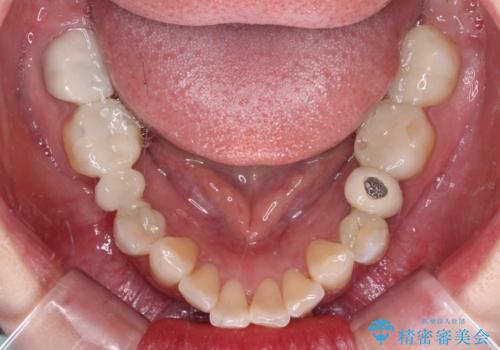

- クラウンから金属の土台が見えてきてしまったとのことで、作り替えを希望して来院された患者様です。

前歯や金属が露出している歯、痛みを感じる歯を中心に、オールセラミッククラウンにて補綴治療することとしました。